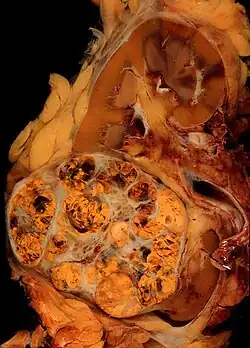

Ovarian cancer

Mutations in DNA repair genes BRCA1 or BRCA2 (active in homologous recombinational repair) are synthetically lethal with inhibition of DNA repair gene PARP1 (active in the base excision repair and in the microhomology-mediated end joining pathways of DNA repair).[40][41]

Ovarian cancers have a mutational defect in BRCA1 in about 18% of patients (13% germline mutations and 5% somatic mutations) (see BRCA1). Olaparib, a PARP inhibitor, was approved in 2014 by the US FDA for use in BRCA-associated ovarian cancer that had previously been treated with chemotherapy.[42] The FDA, in 2016, also approved the PARP inhibitor rucaparib to treat women with advanced ovarian cancer who have already been treated with at least two chemotherapies and have a BRCA1 or BRCA2 gene mutation.[43]